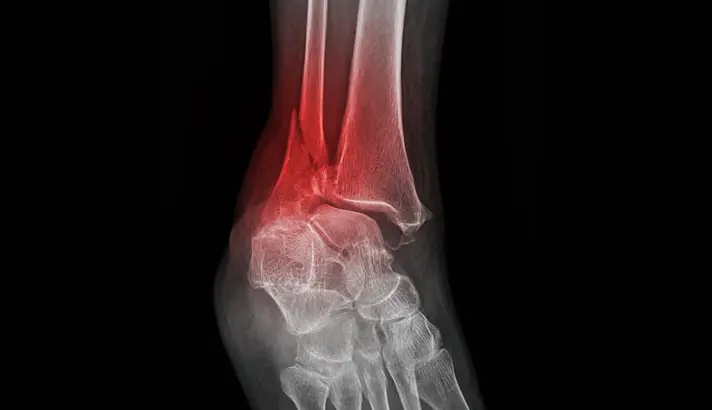

X-ray Imaging

X-rays are the primary imaging tool used to confirm an ankle fracture. Images are typically taken from several angles to identify the location of the break and assess whether the bones remain properly aligned. The X-ray also helps determine whether the ankle joint is stable or if there are signs of widening that suggest associated ligament injury.